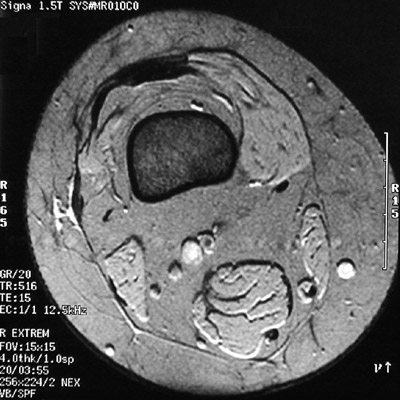

This is a normal axial MRI scan demonstrating the Quadriceps tendon and Suprapatellar synovial bursa and Femur and Vastus medialis and Subcutaneum and Sartorius and Great saphenous vein and Gracilis and Semitendinosus tendon and Semimembranosus and Popliteal artery & vein and Biceps femoris and Deep fascia and Vastus lateralis.